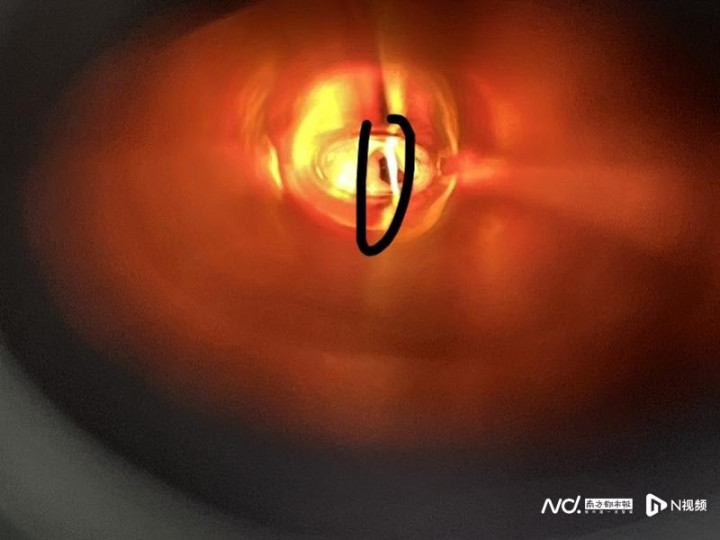

在食谈镜下发现,部分异物在食谈上段且已穿透食谈上缘,而颈部CT不错看到颈段食管左侧异物,部分刺入甲状腺左叶。

经手术取出的鸡爪残余骨渣。